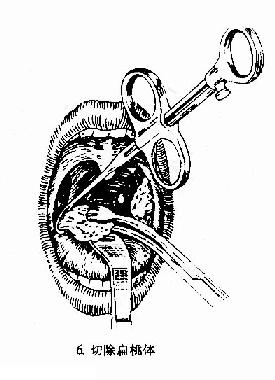

(一)剥离法(dissection method)(图6-2):

图6-2 扁桃体切除术(剥离法)

(3)切除扁桃体:将扁桃体圈套器的钢丝套住扁桃体,同时将扁桃体向上提,钢丝向下压,收紧钢丝圈,绞断扁桃体下极根蒂部分,将扁桃体完整切除下来。